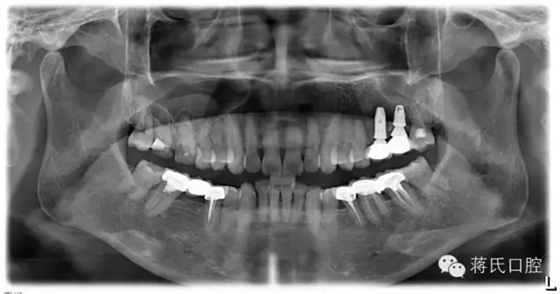

12.修復后全景片